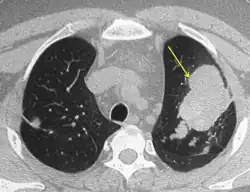

Consolidation and mucoid impaction are the most commonly described radiological features described in ABPA literature, though much of the evidence for consolidation comes from before the development of computed tomography (CT) scans. Tramline shadowing, finger-in-glove opacities and ‘toothpaste shadows’ are also prevalent findings.[30]

When utilising high-resolution CT scans, there can be a better assessment of the distribution and pattern of bronchiectasis within the lungs, and hence this is the tool of choice in the radiological diagnosis of ABPA. Central (confined to medial two-thirds of the medial half of the lung) bronchiectasis that peripherally tapers bronchi is considered a requirement for ABPA pathophysiology, though in up to 43% of cases there is a considerable extension to the periphery of the lung.[7]

Mucoid impaction of the upper and lower airways is a common finding.[7] Plugs are hypodense but appear on CT with high attenuation (over 70 Hounsfield units[31]) in up to 20% of patients. Where present it is a strong diagnostic factor of ABPA and distinguishes symptoms from other causes of bronchiectasis.[13]

CT scans may more rarely reveal mosaic-appearance attenuation, centrilobular lung nodules, tree-in-bud opacities and pleuropulmonary fibrosis (a finding consistent with CPA, a disease with ABPA as a known precursor).[7] Rarely other manifestations can be seen on CT scans, including military nodular opacities, perihilar opacities (that mimic hilar lymphadenopathy), pleural effusions and pulmonary masses. Cavitation and aspergilloma are rarer findings, not exceeding 20% of patients, and likely represent a shift from ABPA to CPA if accompanied by pleural thickening or fibrocavitary disease.[13]